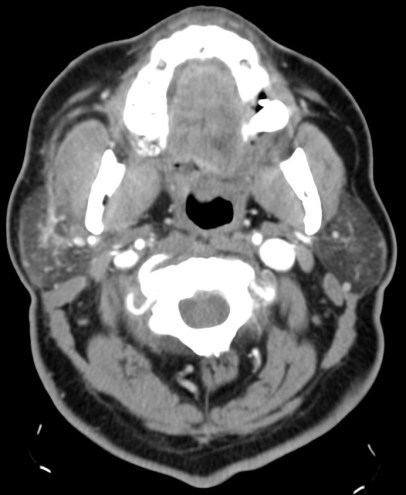

LINFADENITIS CERVICAL

Afectación inflamatoria-infecciosa del tejido linfoide cervical.

Mayor prevalencia en inmunosuprimidos.

Clínica: masa cervical + fiebre, dolor, signos de flogosis local.

TC con contraste:

- Ganglios aumentados de tamaño con o sin necrosis central asociada, uni o bilaterales que pueden confluir formando masacotes adenopáticos en una o más de las cadenas linfáticas cervicales.